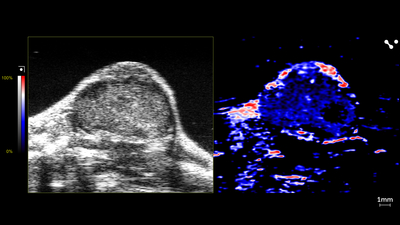

Nanoparticle distribution in tumor

High-resolution ultrasound (left) and spectrally unmixed photoacoustic (right) image of a subcutaneous tumor showing nanoparticle distribution (yellow) as well as oxygenated (red) and deoxygenated (blue) hemoglobin signal.